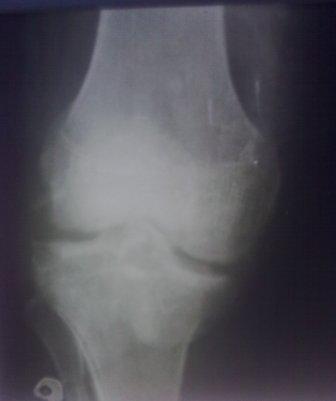

Сегодня обратился больной 35л. Травму получил 3 мес.назад, упал в яму, лечился в отдаленном районе гипсовой повязкой, 1 месяц назад гипс сняли , и больной начал ходить с нагрузкой, постепенно появилась деформация коленного сустава, неустойчивость  и боли. Локально: деформация коленного сустава, голень смещена кзади- типа подвывиха,    разгибание 170гр. Сгибание  150гр.симптомов повреждение боковых коллатеральных

и крестообразных связок определить не удается из-за боли и контрактуры.

Первичных снимков пока нет, обещали принести, имеется снимки через 2 месяца после травмы без гипса, недельной давности снимки в прямой проекции и К Т. Похоже, что импрессия  переднемедиальной  части внутреннего мыщелка б/берцовой кости, отрыв межмыщелкового возвышения.